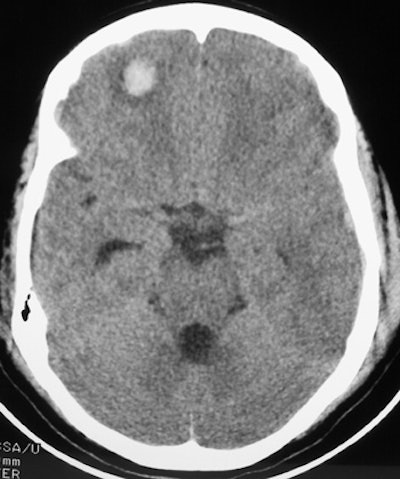

![]() |

| Here, the subdural hematoma (right) is due to venous bleeding on the surface of the brain. This results in a space-occupying lesion with mass effect, shifting brain tissue to the left. The subarachnoid hemorrhage is due to arterial bleeding within the meninges lining the surface of the brain. Both types of bleeding can be seen following blunt trauma to the head. Images courtesy of Dr. John Cameron, University of Miami. |